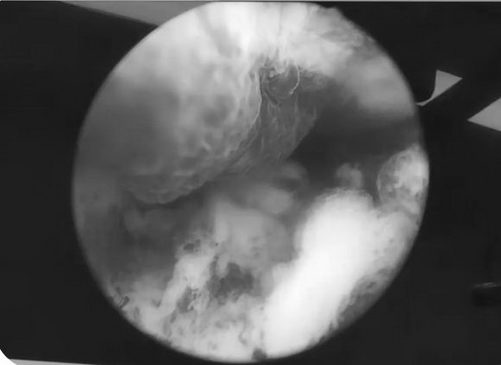

通常情况下有症状的息肉均建议手术切除,无症状的息肉可选择期待治疗,每6个月复查超声,观察其大小变化。宫腔镜下子宫内膜息肉切除技巧取决于息肉大小和宫腔镜设备。

日间手术操作需要经过术前细致的评估、手术精湛的技术、术后贴心的护理才能完成。日间手术具备时间短,效率高的特点,不过虽然时间短,但不能有丝毫的马虎。与常规入院治疗一样要制定时间、手术间和术前检查。手术流程实行专人负责制,以保证手术质量与安全。手术制定的标准更加精细化、人性化。包括根据不同的实际情况确定术式和处理方法。除了保证医疗技术的安全性,青岛新世纪妇儿医院妇科医护团队从术前检查开始,到手术环节的把控、再到术后照护与沟通的各个方面都做得更加细致、完善。现青岛新世纪妇儿医院妇科目前已开展“宫腔镜内膜息肉切除”、“宫腔镜检查 ”等日间手术项目。